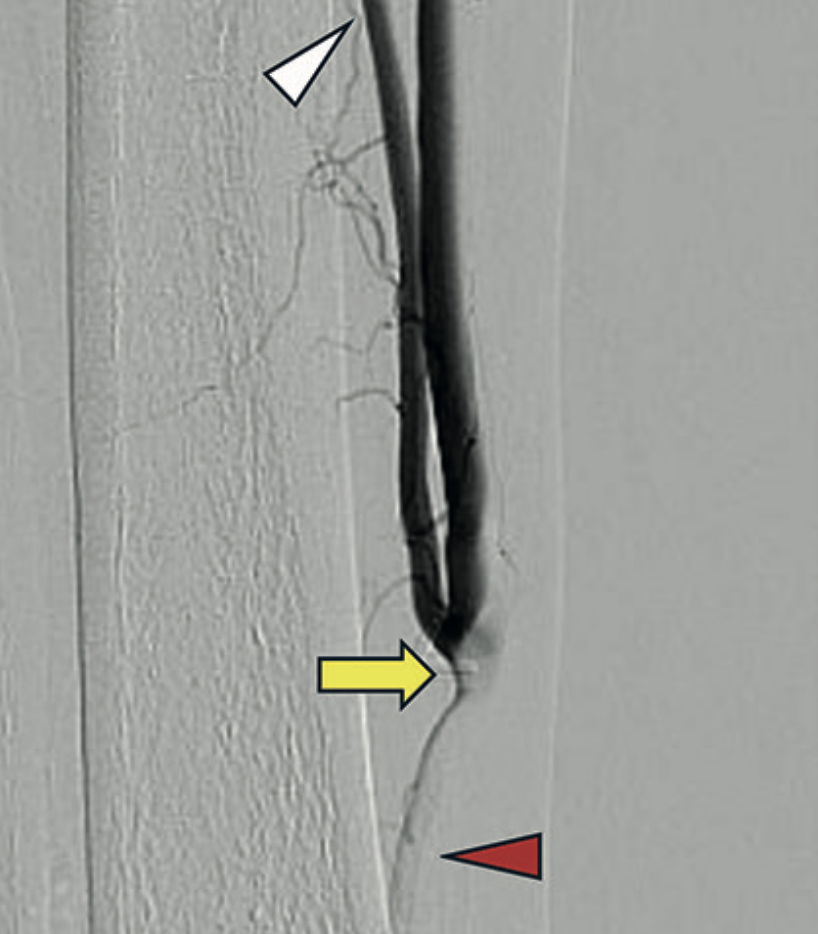

Caso: varón de 73 años con isquemia crítica de miembro inferior derecho, previamente tratado con endarterectomía femoral (EF) y bypass con injerto autólogo (BPIA). Durante el seguimiento ecográfico, se detectó una restenosis severa de AFC y de la anastomosis proximal del BPIA, en un contexto de IH por intervenciones previas. Se realizó un TE mediante angioplastia con balón recubierto con droga (DCB-PTA) de ambas lesiones, a través de acceso braquial. La evolución postoperatoria fue favorable, con alta precoz y permeabilidad mantenida del bypass a 12 meses de seguimiento clínico y ecográfico, sin recurrencia de síntomas.

Discusión: este caso ilustra la factibilidad y efectividad del TE con DCB-PTA en lesiones recurrentes de AFC asociadas a BPIA en fallo, especialmente en situaciones de IH. El seguimiento ecográfico riguroso y la adecuada selección de pacientes son claves para optimizar los resultados a mediano plazo en el TE de lesiones femorales complejas.